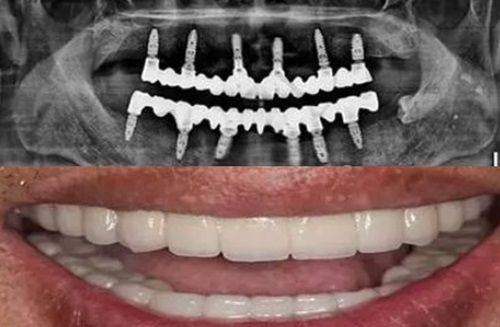

在网络上,也有特别多患者分享了自己在该医院进行树脂贴面治疗的经历。他们上传了治疗前后的对比照片,让更多人直观地看到了树脂贴面的神奇成效。这些真实的实例和好评,进一步提升了医院的口碑和有名度。